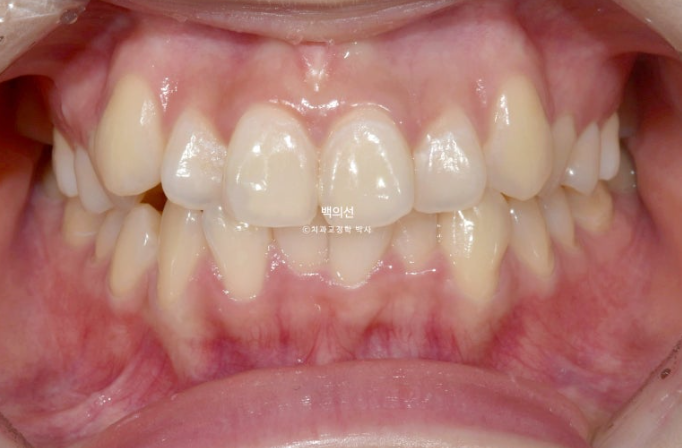

2년 전 5월, 인비절라인 교정을 위해 내원한 환자분입니다.

23.05

송곳니 덧니가 심한편입니다.